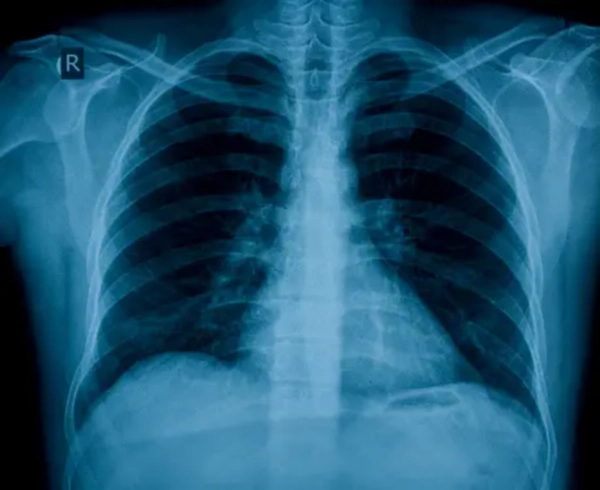

심혈관 질환과 왼쪽 갈비뼈 아래 통증

심혈관 질환 역시 왼쪽 갈비뼈 아래 통증의 원인이 될 수 있습니다. 특히, 심장과 관련된 문제는 생명에 직결될 수 있어 주의가 필요합니다.

🔹 협심증

협심증은 심장에 혈액을 공급하는 관상동맥이 좁아져서 발생하는 통증으로, 주로 가슴 중앙이나 왼쪽 가슴에서 시작되어 갈비뼈 아래까지 통증이 느껴질 수 있습니다. 이러한 통증은 운동이나 스트레스 상황에서 악화될 수 있습니다.

🔹 심근경색

심근경색은 관상동맥이 완전히 막혀 심장 근육이 손상되는 질환으로, 심한 가슴 통증과 함께 왼쪽 갈비뼈 아래 통증을 유발할 수 있습니다. 이러한 통증은 종종 식은땀, 메스꺼움, 어지러움 등을 동반할 수 있습니다.